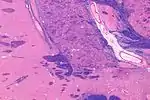

![]() Intermediate magnification micrograph of the nucleus basalis. LFB-HE stain. | |

The nucleus basalis in humans is a somewhat diffuse collection of large cholinergic neurons in the basal forebrain.[2] The main body of the nucleus basalis lies inferior to the anterior commissure and the globus pallidus, and lateral to the anterior hypothalamus in an area known as the substantia innominata.[1] Rostrally, the nucleus basalis is continuous with the cholinergic neurons of the nucleus of the diagonal band of Broca.[1] The nucleus basalis is thought to consist of several subdivisions based on the location of the cells and their projections to other brain regions.[2] Occasional neurons belonging to the nucleus basalis can be found in nearby locations such as the internal laminae of the globus pallidus and the genu of the internal capsule.[1]